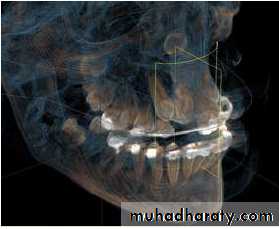

CT Scan

By Ericson & Kurol Used to diagnose the exact

position of an impacted tooth.

Clear serial radiographs may be

taken at graduated depth in any

part of human body in this

method.

This technique allows the

elimination of superimposition

of other structures.

It is however rarely used in the

diagnosis of impacted teeth

because of

(1) Large radiation dosage.

CBCT

Cone beam

computedtomography

(or CBCT, also

referred to as C-arm

CT, cone beam

volume CT, or flat

panel CT) is a

medical imaging

technique consisting

of X-ray computed

tomography where

the X-rays are

conventional radiography does

information.76

not provide sufficient

CBCT is more accurate than

conventional techniques inlocalising impacted maxillary

canines.

CBCT is more reliable than

conventional techniques There is no robust evidence

that supports using CBCT as

the first line imaging technique.

We should only use it when

Cone-beam computed tomography vs conventional radiography in visualization

of maxillary impacted-canine localization: A systematic review of comparativestudies. Ehsan Eslami et al. Am J Orthod Dentofacial Orthop 2017;151:248-58